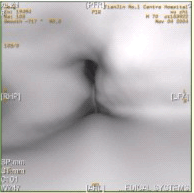

患者男,60岁,声音嘶哑半年,CT表现如下图。

[单选题]患者男,60岁,声音嘶哑半年,CT表现如下图。诊断正确的是A.声门区喉癌B.声门上喉癌C.喉正常表现D.喉结核E.喉乳头状瘤